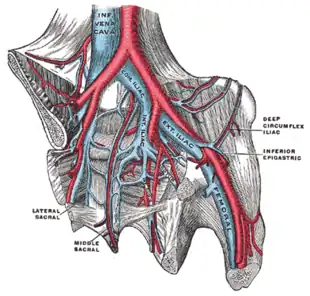

DVT often develops in the calf veins and "grows" in the direction of venous flow, towards the heart.[42][103] DVT most frequently affects veins in the leg or pelvis[9] including the popliteal vein (behind the knee), femoral vein (of the thigh), and iliac veins of the pelvis. Extensive lower-extremity DVT can even reach into the inferior vena cava (in the abdomen).[104] Upper extremity DVT most commonly affects the subclavian, axillary, and jugular veins.[11]